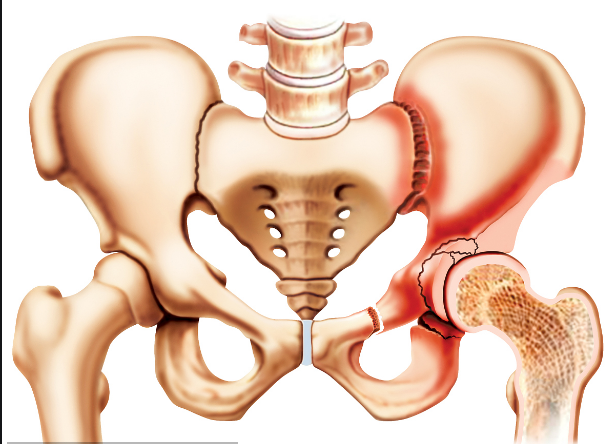

人體的髖關(guān)節(jié)是一個(gè)杵臼關(guān)節(jié),就像我們生活中常見的器物杵臼。“杵”就是我們的股骨頭,而“臼”就是指我們的“髖臼”。我們知道,正常情況下,“杵”是嵌在“臼”里面的,有豐富的肌肉保護(hù)著,但是,當(dāng)“臼”的結(jié)構(gòu)不正常時(shí),“杵”在肌肉的作用下就會從“臼”里慢慢跑出來,導(dǎo)致無法正常發(fā)揮作用。近日,瀘州市中醫(yī)院骨三科開展的市屬醫(yī)院首例髖臼周圍截骨術(shù)PAO, 就成功為一名成年患者解決了“杵”與“臼”結(jié)構(gòu)不正常的問題。

“髖臼發(fā)育不良其根源在嬰幼兒時(shí)期已經(jīng)存在,由于未及時(shí)發(fā)現(xiàn)或治療不徹底而殘留下來 。”瀘州市中醫(yī)院骨三科主任、主任中醫(yī)師李彬介紹,肖女士的髖臼因發(fā)育不良,淺且覆蓋少,因此,造成她的髖臼對位不好。在走路時(shí),因?yàn)榱W(xué)原因,髖關(guān)節(jié)發(fā)生摩擦因而產(chǎn)生強(qiáng)烈的疼痛,如果沒有得到及時(shí)的根治性治療,她的病情將慢慢發(fā)展為軟骨炎,最終發(fā)生骨性關(guān)節(jié)炎,影響關(guān)節(jié)功能活動(dòng),最后不得進(jìn)行髖關(guān)節(jié)置換。